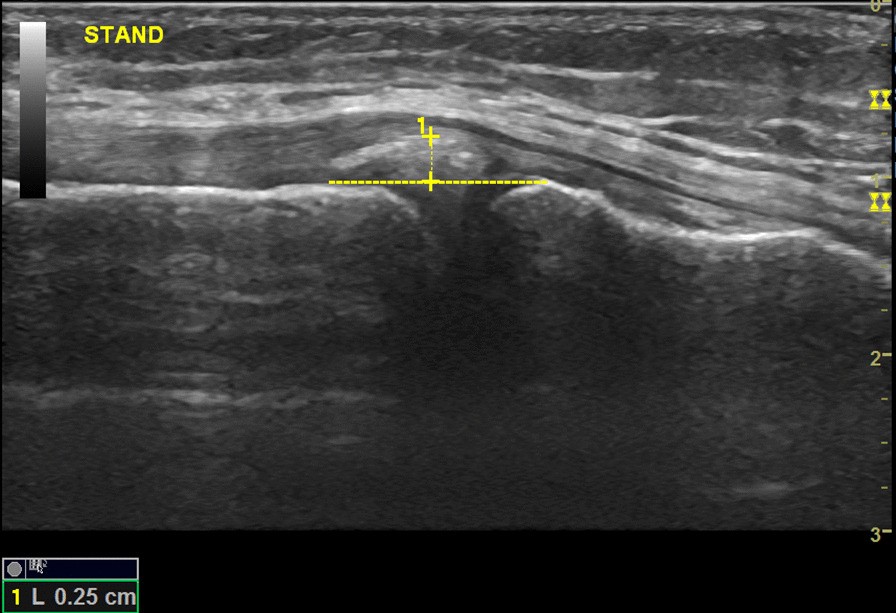

Fig. 1From: Sonographic evaluation of the degree of medial meniscal extrusion during Thessaly test in healthy kneesSonography of the medial meniscus deep to the MCL while standingBack to article page